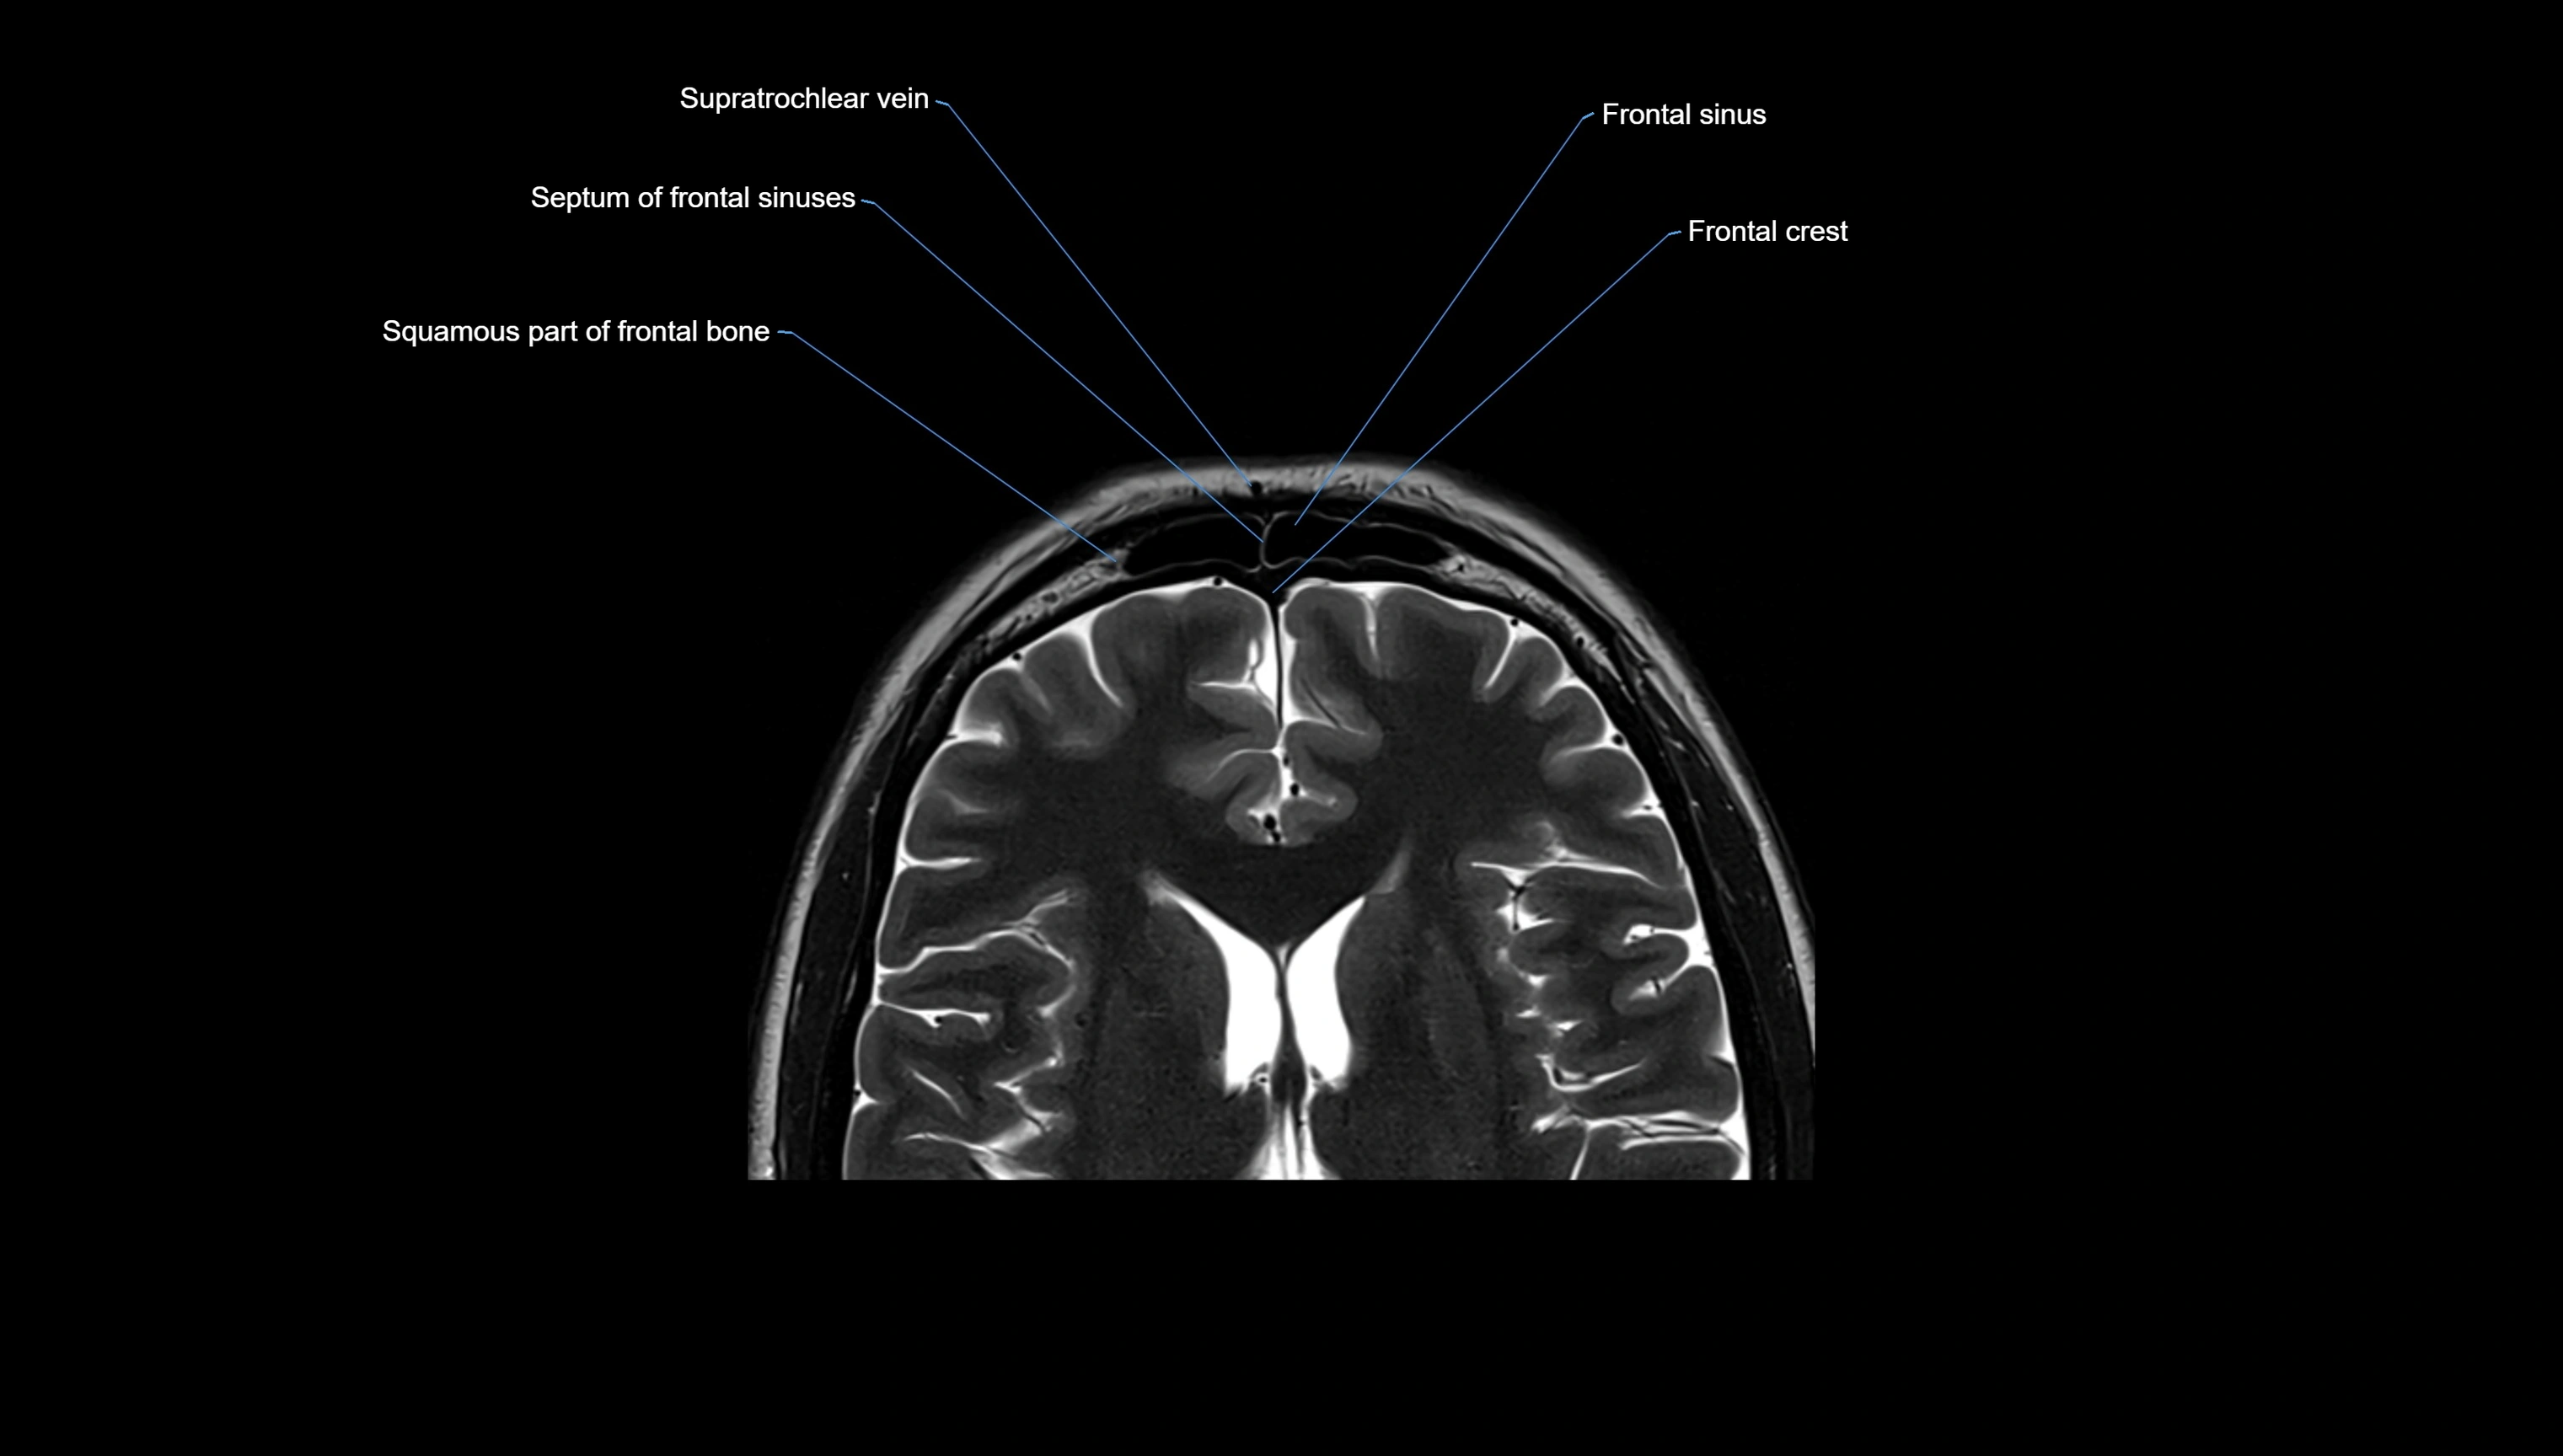

- Frontal sinus

- Supratrochlear vein